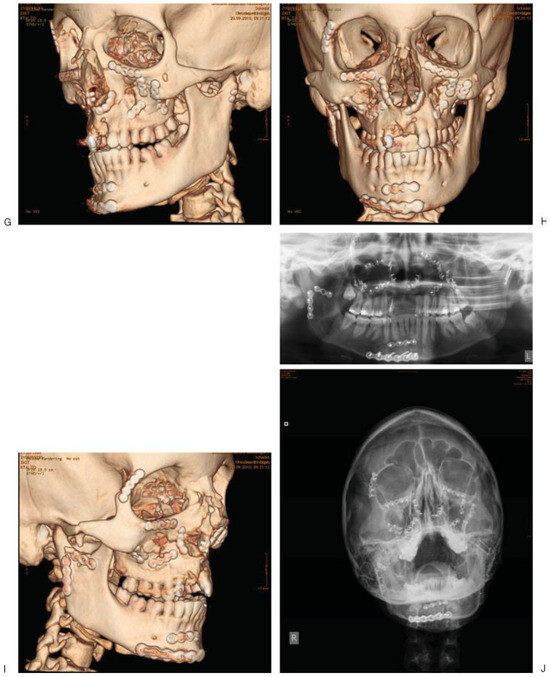

The CMF Trauma Registry at the University Hospital of Innsbruck, Austria was created in 1991 to facilitate prospective and retrospective data collection. All CMF trauma, simple and complex, is listed. Figure 1A–J displays radiographic images of a case representative for the complexity of diagnostic assessment, categorization, and subsequent treatment allowing both excellent reconstruction and superb wound healing. Injury surveillance and research data at this center reflect the whole spectrum of CMF trauma. Its aim was to outline and thereby reveal variables responsible for high-risk conditions resulting in injury, especially CMF injury, in the Alps by identifying, describing, and quantifying trauma. Five main causes of injury exist, namely work, traffic, assaults, sports, and activities of daily life (ADL) [8]. The aim of this study was to assess CMF trauma by evaluating data on patients with facial bone fractures, dentoalveolar trauma, and soft tissue injuries and to investigate the impact of the five main causes of facial injury. This work also reflects statistical patterns of CMF trauma in relation to accident causes using logistic regression analyses.

Figure 1.

Selected preoperative radiographic CT images in right (A) oblique, (B) frontal, and (C) left oblique view, of a female patient 22 years of age with complex panfacial fractures of midface and mandible. Image (D) shows a coronal cut of dislocated fractures of the right mandibular condyle and left mandibular head. Image (E) depicts dislocated Le Fort I, zygoma and orbital floor fractures. Image (F) reveals the extent of the orbital floor fracture in the anterior posterior direction. Selected postoperative radiographic CT images in (G) right oblique, (H) frontal, and (I) left oblique view, and (J) conventional radiographs, show the great current options of matrix plates and screws for treating CMF Trauma.